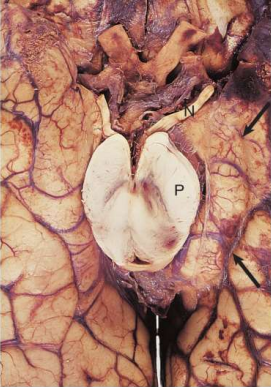

What are the different types of intracranial herniation?

A

Subfalcine- herniation under flax cerebri

Transtentorial- medial temporal lobe herniates over tentorium cerebelli

Tonsillar- cerebellum herniates through foramen magnum

What happens in a trans-tentorial herniation?

Uncus/medial part of the parahippocampal gyrus

through the tentorial notch:

- Damage to CN 3 (oculomotor nerve) on

ipsilateral (same) side

- Occlusion of the blood flow in posterior cerebral

and superior cerebellar arteries

resulting in ischaemia.

COMMON mode of death (tumours and ICH)

Duret haemorrhage- haemorrhage into brainstem due to brain being pushed downwards which causes the pontine vessel branches to be compressed

What happens in a tonsillar herniation?

Cerebellar tonsils pushed into foramen magnum compressing the brainstem